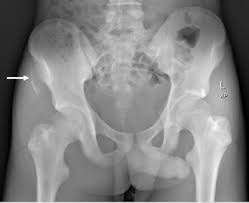

Anterior Superior Iliac Spine, Appendicular Skeleton And Joints Ppt Download : It can be palpated by putting the hands at the top of the hipbones and following the bony margins toward the front of the hips.. The posterior border of the ala, shorter than the anterior, also presents two projections separated by a notch, the posterior superior iliac spine and the posterior inferior iliac spine. Jun 28, 2021 · insertion: Asis, anterior superior iliac spine. Diagnosis is made with pelvis radiographs that shows an avulsion off the aiis. Anterior angulation of the coccyx may be a normal variant but poses a diagnostic challenge for those considering coccygeal trauma.

It provides attachment for the inguinal ligament , the sartorius muscle , 1 4 and the tensor fasciae latae muscle. The anterior superior iliac spine (asis) is the most anterior part of the iliac crest. An anterior superior iliac spine (asis) avulsion is a traumatic avulsion of the asis due to a sudden and forceful contraction of the sartorius and tensor fascia lata that occurs in young athletes. Asis, anterior superior iliac spine. This part is the most observable and palpable of the pelvis. The posterior border of the ala, shorter than the anterior, also presents two projections separated by a notch, the posterior superior iliac spine and the posterior inferior iliac spine. Diagnosis is made radiographically with displaced injuries but ct/mri may be required to diagnosis nondisplaced fractures. It provides attachment for the inguinal ligament, and the sartorius muscle. An anterior inferior iliac spine (aiis) avulsion is an apophyseal avulsion injury seen in adolescent athletes as a result of eccentric contraction of the rectus femoris. It refers to the anterior extremity of the iliac crest of the pelvis. The anterior superior iliac spine refers to the anterior extremity of the iliac crest of the pelvis. Outer lip of anterior iliac crest, anterior superior iliac spine (asis) insertion: Classification four types of coccyx have been described:

Outer lip of anterior iliac crest, anterior superior iliac spine (asis) insertion: Aug 29, 2017 · aiis, anterior inferior iliac spine; Asis, anterior superior iliac spine. The posterior border of the ala, shorter than the anterior, also presents two projections separated by a notch, the posterior superior iliac spine and the posterior inferior iliac spine. An anterior superior iliac spine (asis) avulsion is a traumatic avulsion of the asis due to a sudden and forceful contraction of the sartorius and tensor fascia lata that occurs in young athletes. The tensor fasciae latae and sartorius muscles of the thigh have their origins at the anterior superior spine. An anterior inferior iliac spine (aiis) avulsion is an apophyseal avulsion injury seen in adolescent athletes as a result of eccentric contraction of the rectus femoris. It provides attachment for the inguinal ligament, and the sartorius muscle. The posterior superior iliac spine serves for the attachment of the oblique portion of the posterior sacroiliac ligaments and the multifidus. It provides attachment for the inguinal ligament , the sartorius muscle , 1 4 and the tensor fasciae latae muscle. It can be palpated by putting the hands at the top of the hipbones and following the bony margins toward the front of the hips. Classification four types of coccyx have been described: Diagnosis is made radiographically with displaced injuries but ct/mri may be required to diagnosis nondisplaced fractures.